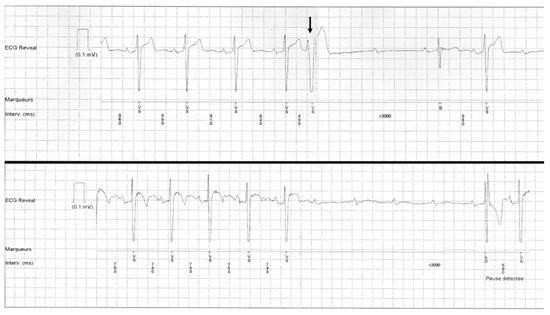

- “Intrinsic” AVB (suggesting AV conduction disease), which may be divided into four categories: Congenital heart block; tachycardia-dependent AVB; PD-AVB; and finally other acquired AVB when the preceding features/conditions are lacking (non-PD-AVB group in our study) as shown in Figure 6. Progressive cardiac conduction disease may be integrated into this last category, and refers to primary genetic degenerative diseases of genetic origin (several mutations have been described, such as in SCN5A of the cardiac sodium channel) [9]. Combined AVB initiation circumstances may be encountered in this “intrinsic” AVB group.